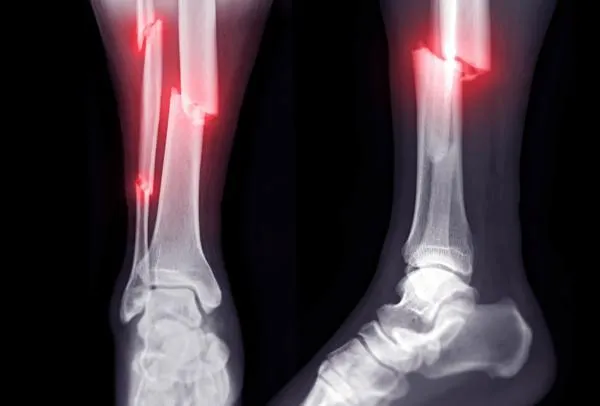

A broken bone is never easy, but some fractures are more complicated than others. A complex fracture refers to a severe break where the bone is shattered into multiple fragments, involves the joints, does not heal properly, or is accompanied by infection or deformity. Unlike simple fractures that usually heal with a plaster cast, complex fractures require specialised orthopaedic care and advanced surgical techniques.

A complex fracture is defined as a bone break that is severe, unstable, or involves complications. These fractures may include:

• Comminuted fractures: bone breaks into three or more fragments.

• Open (compound) fractures: bone pierces the skin, exposing the wound.

• Segmental fractures: multiple breaks in the same bone.

• Intra-articular fractures: fracture extends into the joint surface.

• X-rays: Initial imaging for fracture location and severity.

• CT Scans / MRI: Detailed mapping of bone fragments, joint involvement, or soft tissue injury.